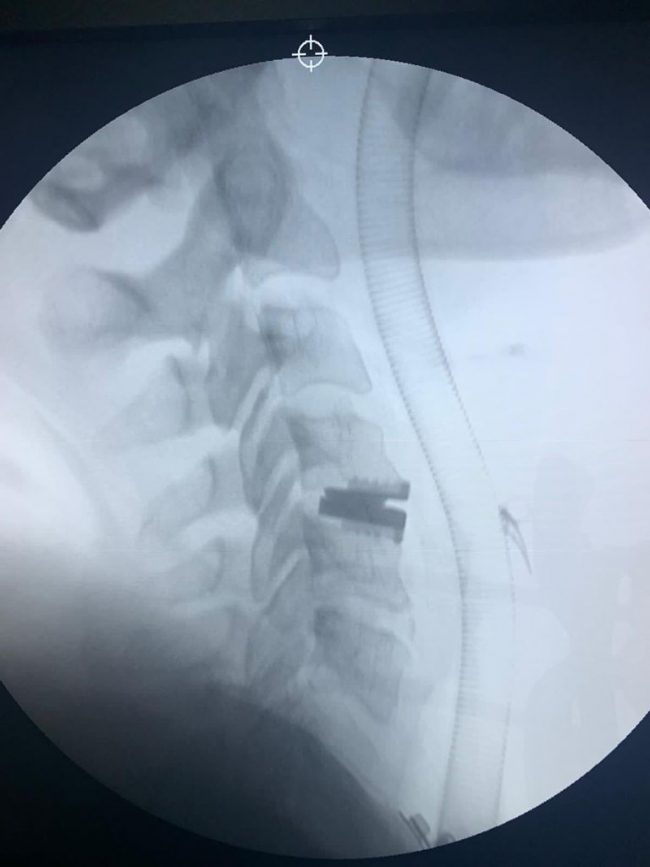

Fuente: Quirónsalud Huelva Es la primera intervención quirúrgica craneal realizada en el Hospital Quirónsalud Huelva Las cefaleas constantes, vértigos, dificultad en la marcha o entumecimiento de los brazos son algunos de los síntomas clásicos en un paciente que sufre la malformación de Arnold-Chiari. El doctor Miguel Ángel Roldán Serrano, neurocirujano del Hospital Quirónsalud Huelva…